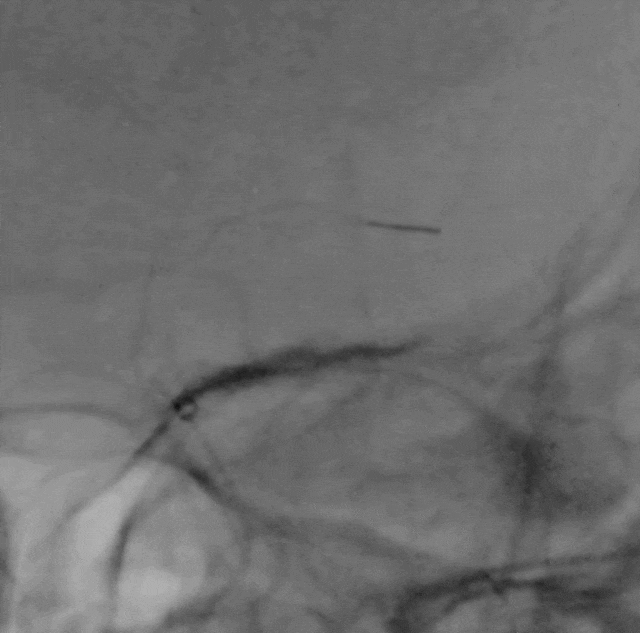

泥鳅导丝、SIM2造影导管、5.5F Introsky X导管鞘同轴下继续跟进,尽可能高到位,随后引入V-18导丝。

Catalyst 6 中间导管在5.5F Introsky X导管鞘内输送顺利,微导丝、微导管超选越过闭塞段。